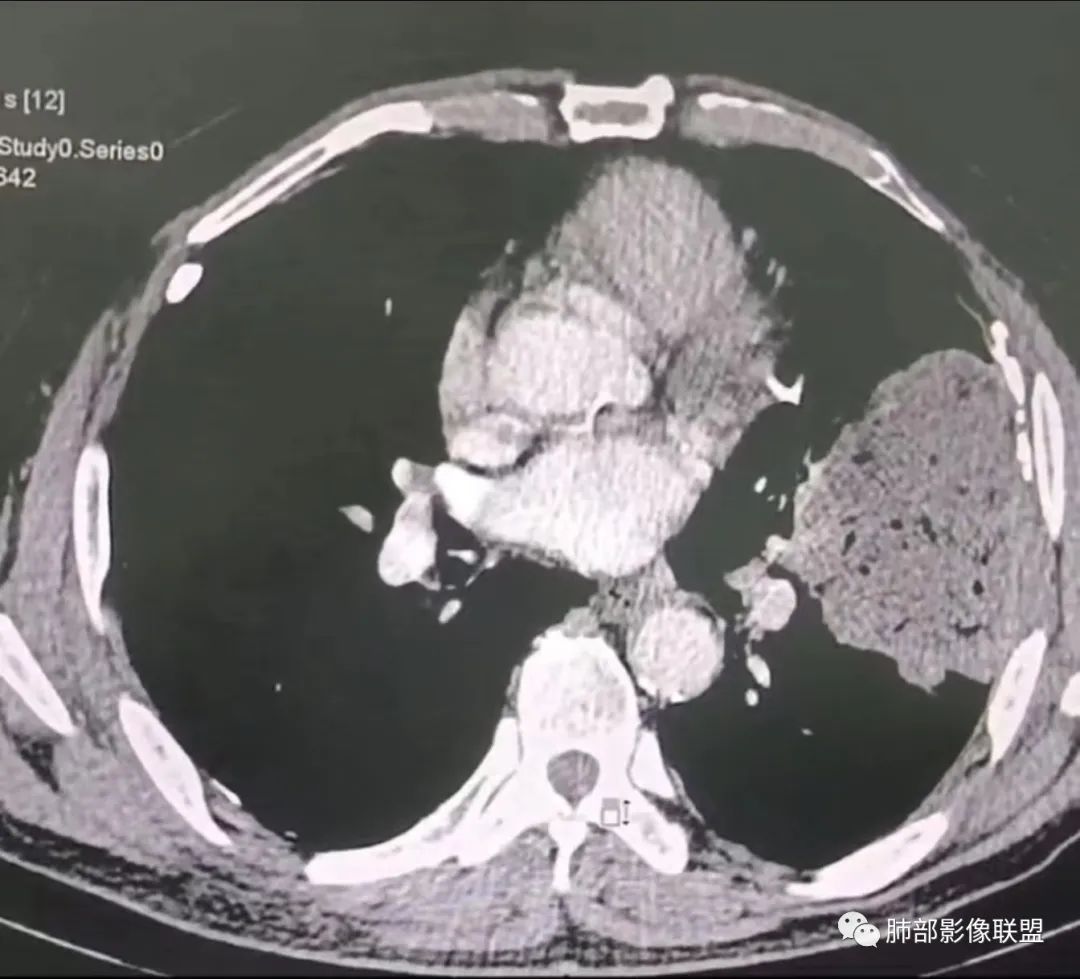

左肺上叶大肿块,膨胀性生长,边界清,密度较低,见部分坏死区,强化弱,肿块见支气管充气V扩张征,分布僵直,枯树枝特点,另一个重要特点血管造影征,淋巴瘤,肿块长轴与胸膜平行,与隐球菌鉴别,隐球荚膜抗原检查,明确诊断经皮肺穿刺。另胸膜钙化(问诊既往有无患胸膜炎病史)。

老年男性,糖尿病病史,消瘦、乏力三个月,影像表现左肺上叶胸膜下团块,有一定张力,内部疏松,可见支气管影及坏死区,增强病灶边缘环形强化,内部未见强化,考虑炎性肉芽肿病变,隐球?奴卡?放线菌?鉴别淋巴瘤。

左肺上叶胸膜下肿块,宽基底与胸膜相连,跨叶裂,边缘清晰膨隆,其内支气管充气,部分扩张、僵直,无明显强化,血管造影征,考虑淋巴瘤,鉴别腺癌

左肺胸膜下巨大占位,跨叶裂,宽基底与胸膜相连,胸膜钙化,平扫密度较低,强化不明显,可见内部血管显影,支气管充气征和扩张,考虑为恶性,倾向于淋巴瘤

我要修正一下观点了:仔细看了视频,肿块占位效应明显,对周围血管,支气管有推挤,增强后强化不明显,NSE增高,半年体重下降25公斤,虽然有内部支气管扩张,血管漂浮,边界清楚支持淋巴瘤,但强化太低,膨隆,占位推挤太明显(淋巴瘤一般没有这么明显的占位效应),胸膜关系有载桩,恶病质明显(乏力,半年体重下降了25公斤),NSE也明显增高,就不支持淋巴瘤了。还是考虑外朝内的恶性肿瘤,间质来源的肉瘤伴有神经内分泌分化或者大神泌。

不支持淋巴瘤的有四点:1、对周围血管支气管推挤明显。2、胸膜有栽桩,3、强化太弱(淋巴瘤一般还是中度以上甚至高度强化多见),4、NSE升高明显,体重下降太明显。

我再建一下血管。支气管进入,但是近端推移,堵塞

大肿块,边缘光滑,深分叶

近端支气管堵塞、推移为主

部分类似于脐凹征

内部支气管扩张

肺动脉推移为主,边缘部分进入

4)密度:肿块平扫为软组织密度,由于体积较大,内部常见大片状坏死,可出现不规则厚壁空洞或坏死内多发无壁小空洞,坏死多不均匀:坏死灶内可见如柳絮样的斑片样强化灶,坏死边缘与非坏死区分界不清本例坏死较明显,密度不均匀。

5)肿瘤强化方式:肺部恶性肿瘤强化程度与其血供丰富程度相关,血供丰富多强化明显,反之则较差。由于PSC 周边实性部分富血供及内部黏液变性、坏死,增强后肿块多数呈轻-中度边缘环形强化或不均匀小斑片状强化。国外学者对照病理发现肿瘤细胞或胶原组织增强扫描时强化,无强化的低密度区代表了黏液样变性区和出血坏死区。